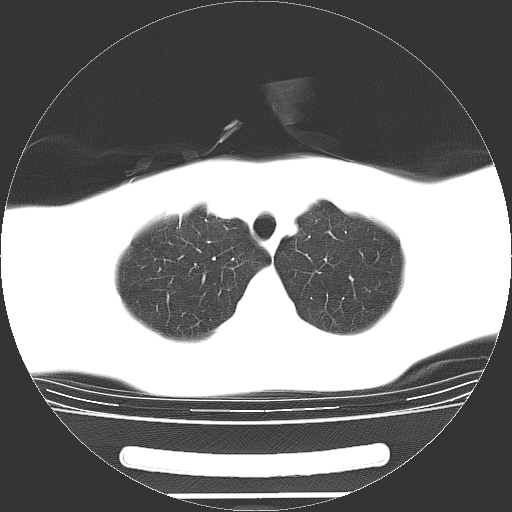

标题: CT19767:男,20岁,右侧气胸行闭式引流术后五天CT检查。 [打印本页]

男,20岁,右侧气胸行闭式引流术后五天ct检查看肺内是否有肺大泡,纵隔窗未见异常,未上传。

1)右侧胸腔闭式引流术后导管留置。2)右肺未见肺大泡。

未见肺大泡,还有微量气体。